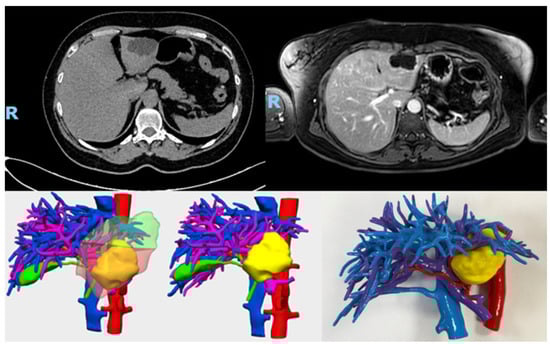

2.2. Acquisition of 3D Models